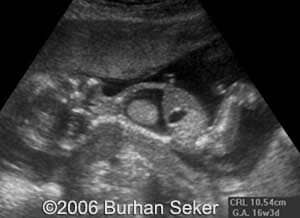

This a fetus with a cystic hygroma diagnosed at 13 weeks and 3 days. Karyotype was normal. The pregnancy was interrupted at 16 weeks.

At 16 weeks.Note the pleural effusion